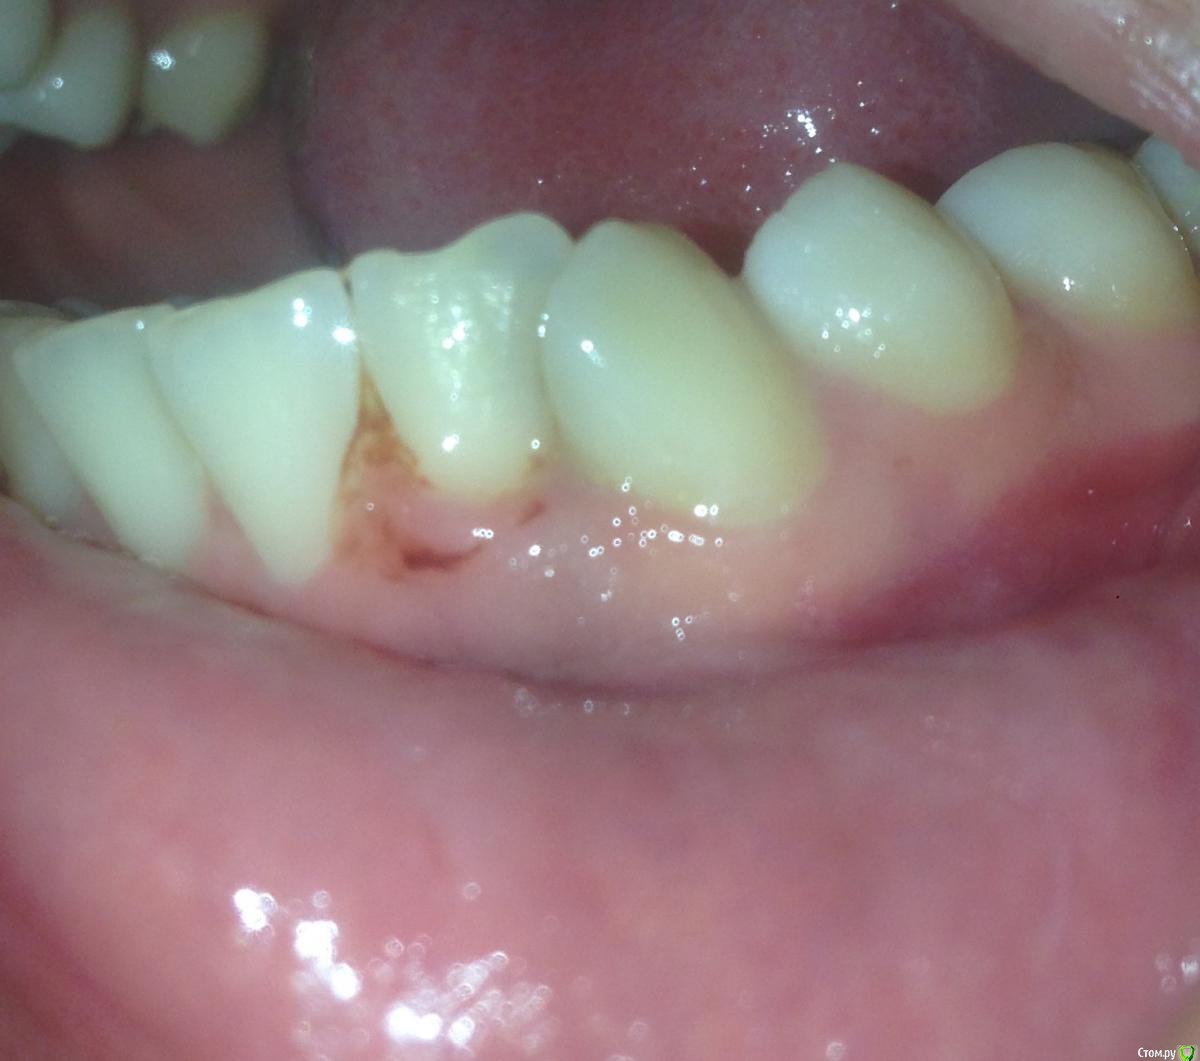

Юл1. Опубликовано 14 февраля, 2020 Поделиться Опубликовано 14 февраля, 2020 Здравствуйте, ситуация такая: 14. 02 пришла лечить 32 зуб, и случайно на снимке обнаружили это. Я была у двух опытных врачей, никто с таким не сталкивался. Мнения расходятся, один доктор говорит удалять, второй не трогать, по возможности сделать кт и наблюдать, делать снимки два раза в год. Я бы удалила, но нет финансовой возможности ставить имплант. Подскажите как быть? Возраст 26 лет, лет 5 назад делала снимок панорамный, зуб был в порядке, травм не было. Ссылка на комментарий

Дмитрий Л. Опубликовано 14 февраля, 2020 Поделиться Опубликовано 14 февраля, 2020 (изменено) Имплант там не особо и встаёт. https://bestendoglenview.com/wp-content/uploads/2012/04/Internal-inflammatory-root-resorption-the-unknown-resorption-of-the-tooth.pdf С рентгеном раз в полгода можно и влипнуть. Если решите наблюдать, то сначала раз в две недели 2 раза, потом раз в 4 недели полгода. Иногда внутрення резорбция корня случается сама по себе (по непонятным науке причинам), но иногда есть пусковые факторы. Кариес-пульпит или травма, в т.ч. окклюзионная (из-за прикуса или бруксизма). Я рекомендую вам обратиться к ХОРОШЕМУ эндодонту и пролечить зуб. Это, конечно же, может вызвать и обострение, и осложнение, но шанс ещё есть и нужно его использовать. По-этому можете ждать пока оно рассосётся или разболится, а можете пытаться спасти. Не отчаивайтесь. В крайнем случае хирурги с нашего форума смогут забрать нижнюю часть зуба, а верхнюю оставить. Успехов! Изменено 14 февраля, 2020 пользователем Дмитрий Л. 1 Ссылка на комментарий